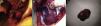

Se decidió someter inicialmente a enucleación tumoral calculando R.E.N.A.L. Score de nefrometría identificándose como lesión de baja complejidad (6 puntos)3. Finalmente se realizó nefrectomía parcial izquierda abierta sin complicaciones técnicas con un tiempo de cirugía de 3h, un tiempo de isquemia caliente de 30min, obteniéndose espécimen de 4.5×3.5×3cm con bordes quirúrgicos negativos (fig. 3).

Figura 3.

A y B. Imágenes transoperatorias de nefrectomía parcial izquierda. C. Producto inmediato de nefrectomía parcial.

Se envió a patología una muestra irregularmente ovoide (fig. 4), una cara café pardo con lesiones exofíticas de consistencia dura con reporte histopatológico de nefroma quístico (fig. 5).

Figura 4.

A. Producto macroscópico tras preparación. B y C. Corte patológico transversal.

Figura 5.

Microfotografía 40X. Hematoxilina-eosina. Características microscópicas del nefroma quístico. Morfología en cabeza de clavo